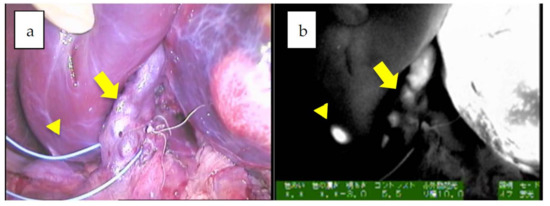

- Yamada, Y.; Hoshino, K.; Mori, T.; Kawaida, M.; Abe, K.; Takahashi, N.; Fujimura, T.; Kameyama, K.; Kuroda, T. Metastasectomy of Hepatoblastoma Utilizing a Novel Overlay Fluorescence Imaging System. J. Laparoendosc. Adv. Surg. Tech. A 2018, 28, 1152–1155. [Google Scholar] [CrossRef] [PubMed]

| 6 | 20 | 19y/F | Pinpoint + PDE neo | Pleural and diaphragm resection | wholly epithelial type and fetal subtype | diffuse | 47 × 38 × 21 mm | 2885 | tumor margin, identification, 28 m |